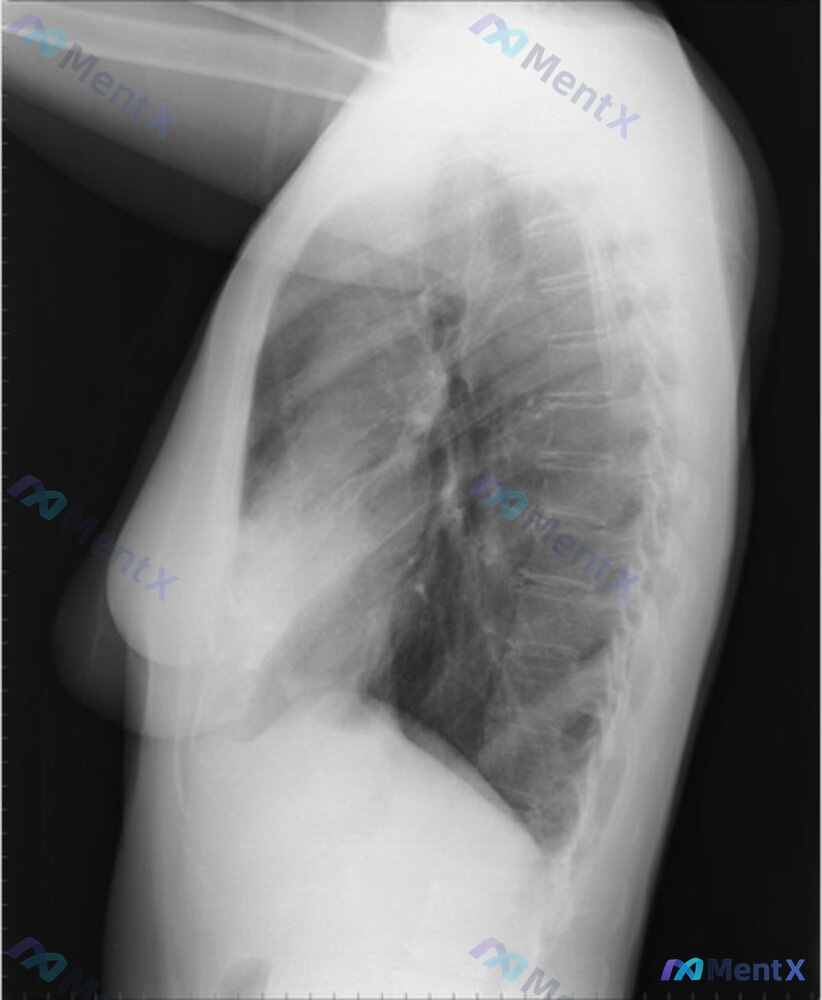

已拍胸部正侧位X光片,影像表现重点:

- 侧位:病灶位于心影前缘后方,右肺中叶解剖位置,呈楔形致密影,未见明确空洞

- 其余肺野、肺门、心影、纵隔、胸膜腔等未见明显异常